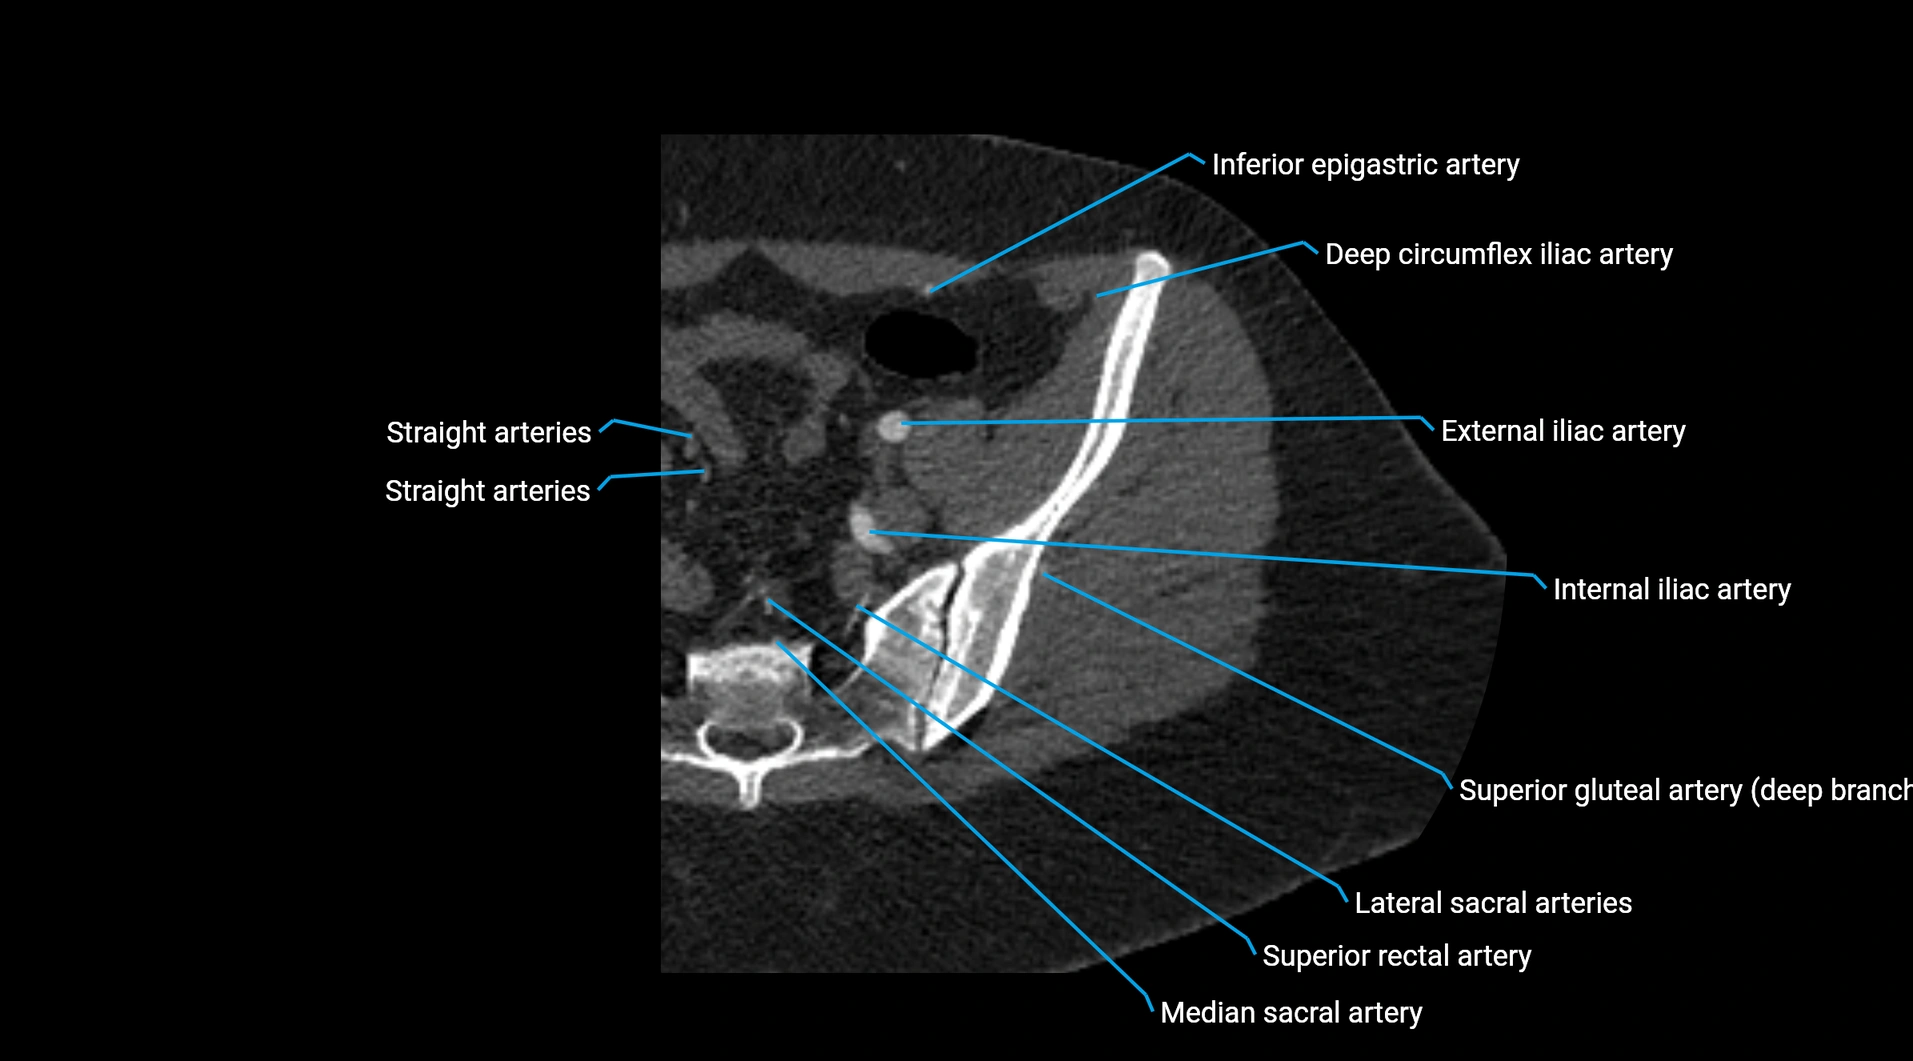

CT images

image